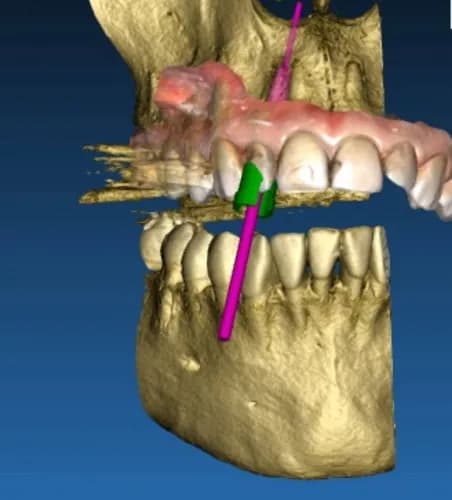

Jeśli odczuwasz dolegliwości, których nie da się jednoznacznie zdiagnozować podczas standardowej wizyty, tomografia komputerowa zębów w Warszawie pozwala dokładnie ocenić stan całej jamy ustnej. Badanie 3D umożliwia szczegółowe zobrazowanie zębów, korzeni, kości oraz tkanek otaczających, dzięki czemu stomatolog w Warszawie może wykryć ukryte stany zapalne, zmiany okołowierzchołkowe czy problemy wymagające leczenia kanałowego lub chirurgicznego. Tomografia jest szybka, bezbolesna i stanowi zaawansowane narzędzie diagnostyczne, szczególnie przy skomplikowanych przypadkach. Na podstawie wyników możliwe jest precyzyjne zaplanowanie leczenia zębów i uniknięcie niepotrzebnych zabiegów. W ramach stomatologii Warszawa możesz skorzystać z nowoczesnej diagnostyki i uzyskać pewną diagnozę. Przez FindOUT możesz bezpośrednio skontaktować się ze stomatologiem, omówić badanie i koszty bez pośredników oraz uzyskać pomoc w swoim języku, co zapewnia komfort i bezpieczeństwo leczenia.